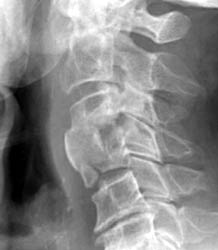

Endplate Fracture

76 y.o male with symptoms of myelopathy, underwent C3,4 ACDF. 1 month later

the patient had complaints of severe dysphagia, feelings of 'food and

liquid getting caught'.

This radiograph take 1 month later demonstrates anterior

extrusion of bone graft material at C3-4 and an endplate fracture at C4. |